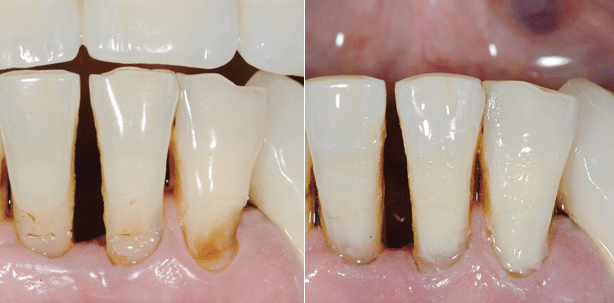

Moderne Füllungssysteme kombinieren die Vorteile von GIZ mit denen von Kompositen. Das zweistufige EQUIA-System (GC) beispielsweise setzt auf eine glasionomerbasierte Füllungskomponente, die mit einem Kompositlack überzogen wird (EQUIA Fil bzw. EQUIA Coat). Der Coat soll zur Optimierung der Werkstoffeigenschaften beitragen und für eine ansprechendere Farbgebung sorgen. Praxisrelevant aus Sicht des Zahnarztes ist vor allem die klinische Leistungsfähigkeit, diesbezüglich hat sich das zweistufige EQUIA-System bereits in mehreren Studien über verschiedene Zeiträume bewährt.6,7,8,9 Hinzu kommen wesentliche Vorteile wie das einfache Handling sowie die vergleichsweise kurze Verarbeitungszeit, zurückzuführen auf die nicht dringende Notwendigkeit eines Kofferdams sowie die Füllungslegung in lediglich zwei Arbeitsschritten: Bulk-Fill-Applikation und Auftragen des Coats (eine komplette EQUIA-Füllung kann laut Herstellerangaben in drei Minuten und 25 Sekunden gelegt werden). Ein weiterer wesentlicher Aspekt ist nicht zu vernachlässigen: Gemäß der Gebrauchsanweisung ist EQUIA u.a. bei Restaurationen der Klasse I, unbelasteten Restaurationen der Klasse II und kaudruckbelasteten Restaurationen der Klasse II (sofern der Isthmus weniger als die Hälfte des Interkuspidalraumes beträgt) anwendbar und darüber hinaus für diese Indikationen über die GKV abrechnungsfähig (ohne Mehrkostenvereinbarung nach den BEMA-Nummern 13a bis 13d).10 Mit Blick auf finanziell „schlechter“ situierte Senioren wie auch auf diverse Zukunftsprognosen – Stichwort „Altersarmut“ – kann dies ein entscheidender Aspekt sein, wenn es um die Wahl des Füllungsmaterials geht. Denn oft genug ist die Entscheidung für oder gegen ein Restaurationsmaterial mit der Zuzahlungsbereitschaft der Patienten verbunden. Hinsichtlich der Indikationsstellungen zeichnet sich EQUIA bei älteren Patienten besonders durch die Eignung für die beschriebene, immer häufiger auftretende Wurzelkaries (Abb. 1 und 2).